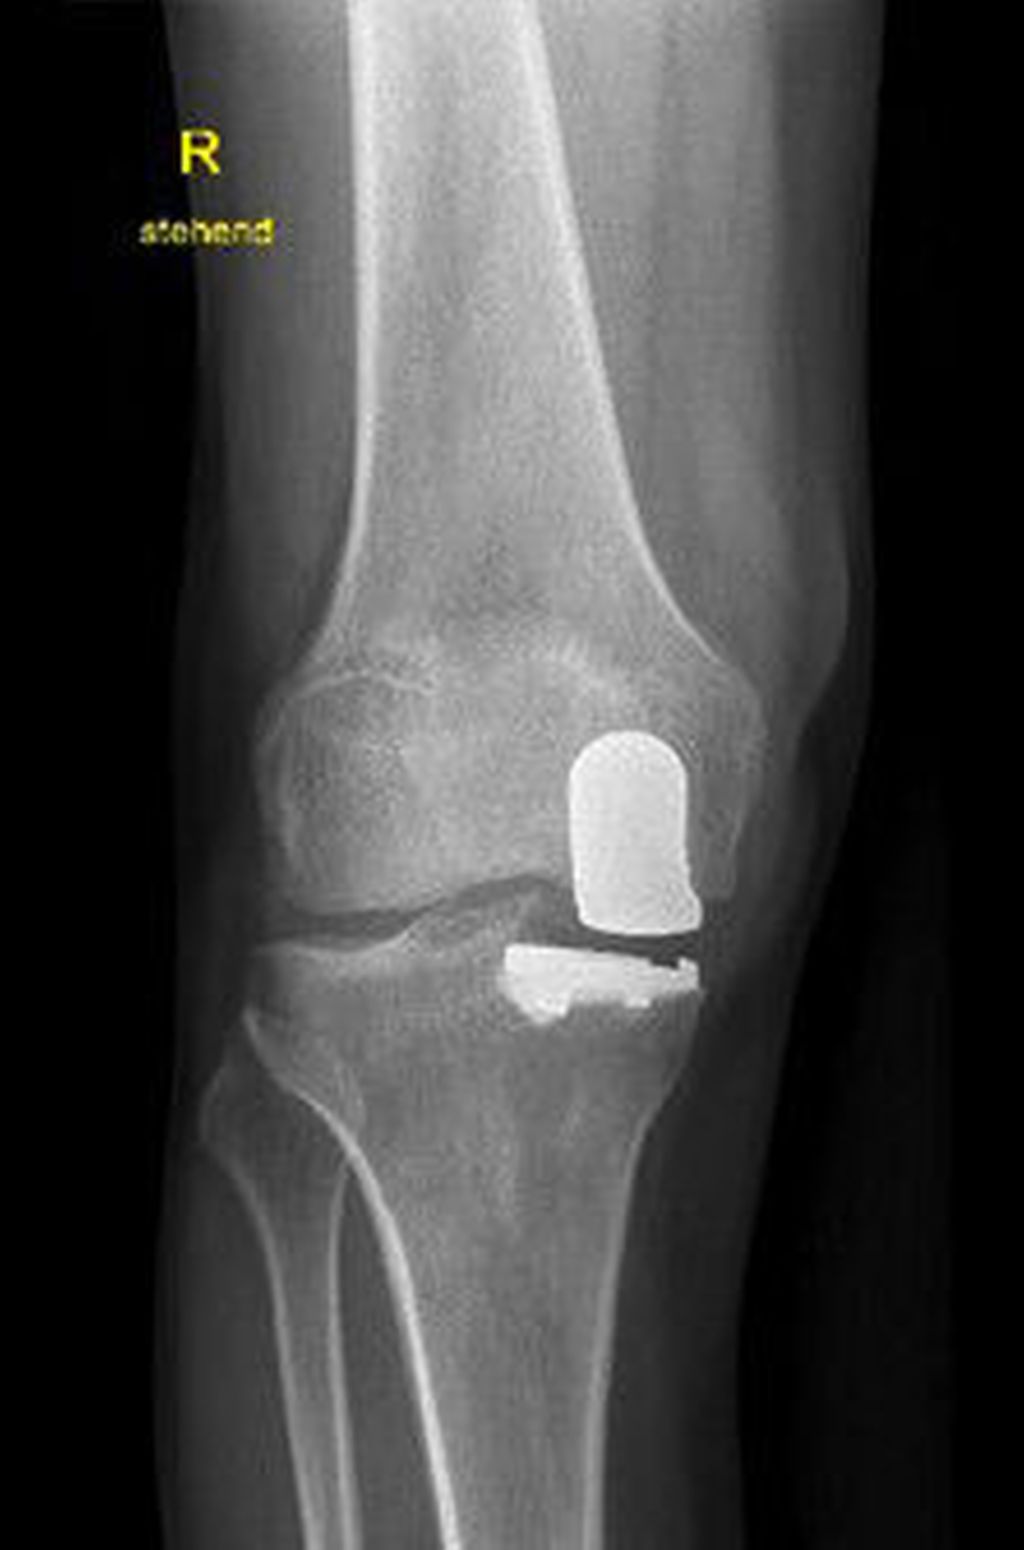

Relevanz der Beinachse bei der Therapie von degenerativen Meniskusläsionen